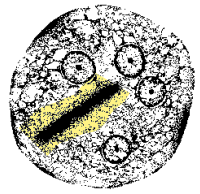

Sarcocystis spp (mature oocyst)

Sarcocystis spp (single sporocyst)